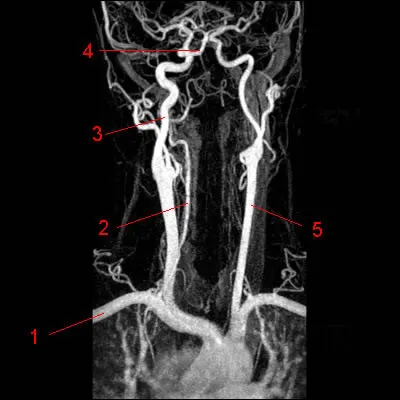

Le scanner peut aussi servir à visualiser les gros vaisseaux du corps humain tels que l'aorte ou les artères carotides. Pour cela, on va utiliser des produits de contraste iodés, qui vont venir opacifier les vaisseaux et ainsi sensibiliser la détection de lésions vasculaires. À quoi correspond le petit 5 sur cet angioscanner ?